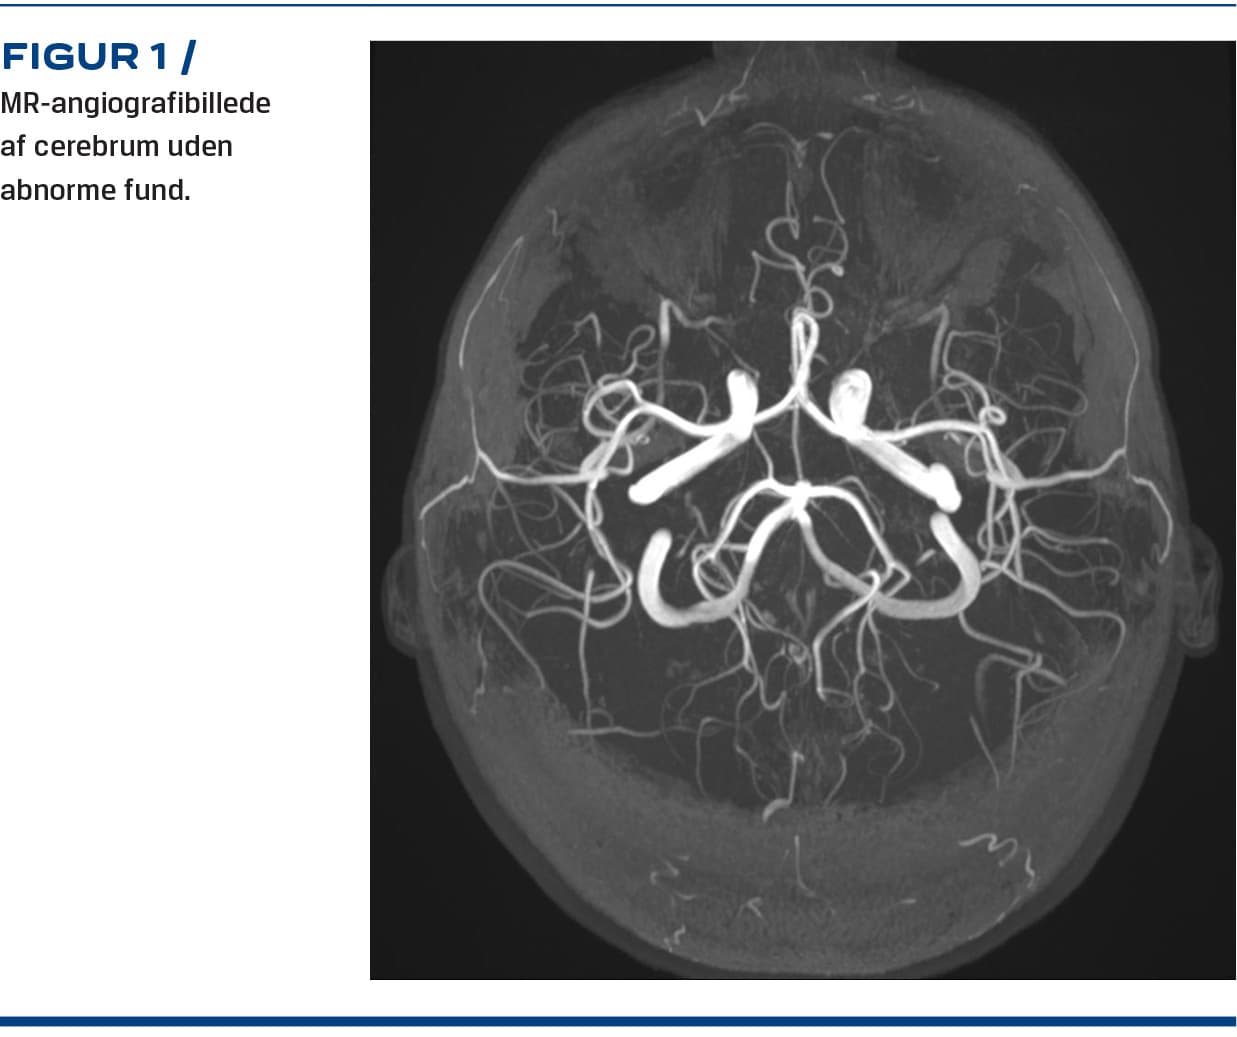

Han blev i de følgende dage tiltagende irritabel og vredladen, og der blev påbegyndt intravenøs behandling med methylprednisolon og immunglobulin, da autoimmun encefalitis ikke kunne udelukkes, samtidig med at HaNDL-syndrom blev overvejet som en mulig differentialdiagnose. Efter negative svar på de resterende undersøgelser og en supplerende MR-angiografi af cerebrum med normalt resultat (Figur 1) var alle kriterierne for HaNDL-syndrom opfyldt (Tabel 1). I de følgende dage oplevede patienten bedring uden yderligere anfald. Han blev udskrevet i velbefindende og havde efterfølgende ikke recidiv i over seks måneder.

Parakliniske undersøgelser ved HaNDL-syndrom viser forbigående lymfocytær pleocytose og øget protein i CSV uden påviselig ætiologi [1, 2]. Radiologiske undersøgelser af hjernen er uden specifikke forandringer og viser som oftest normale forhold [4]. De fleste af patienterne har EEG-forandringer med diffus eller fokal lavfrekvent aktivitet [2, 4]. Årsagen til HaNDL-syndrom er fortsat ukendt, men der er teorier om, at den kan være postinfektiøs inflammatorisk, autoimmun eller vasomotorisk som ved migræne [3, 5].